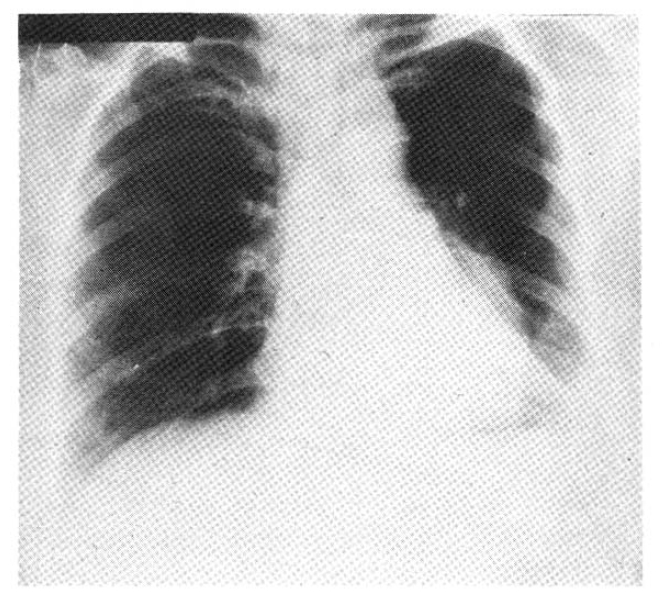

Five weeks before admission she began to cough up blood-streaked sputum. In a recumbent position she suffered from mild dyspnea and wheezing respiration intermittently. Ten days before admission she coughed up frank blood. At the time of admission, the physical examination revealed wheezing and decreased breath sounds in the left lower lung field. Mucocutaneous lesions and palpable lymph nodes were not present. Chest roentgenogram showed left lower lobe collaps (Fig. 2). Laboratory data were normal except for lactic dehydrogenase (LDH) of 414 IU/L. Liver scan was normal. Four repeated sputum cytologic examinations were negative for malignant cells. Pulmonary function tests showed a moderate restrictive pattern. On bronchoscopy, a fungating, dark grayish, irregularly surfaced endobronchial mass at the orifice of the left lower lobe bronchus nearly completely occluding the lumen (Fig. 3) was found. Bronchoscopic biopsy revealed metastatic malignant melanoma (Fig. 4). Computed tomography of the chest showed left lower lobe collapse and aortic invasion (Fig. 5). So palliative chemotherapy with dimethyl triazeno imidazole carboxamide (DTIC) was given as a five day schedule and she was discharged.